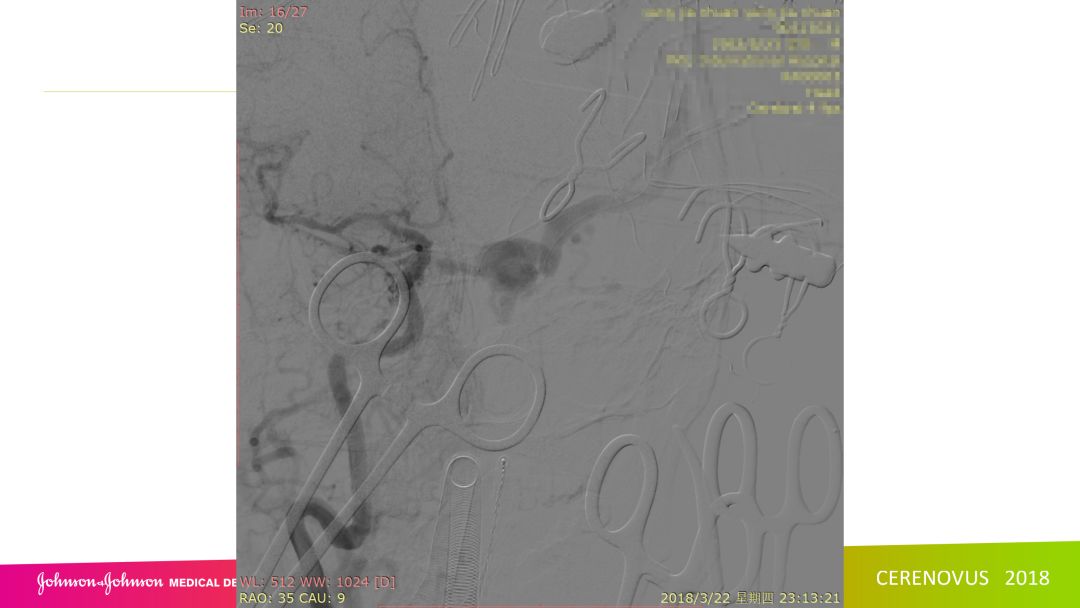

复合手术治疗海绵窦区硬脑膜动静脉瘘一例